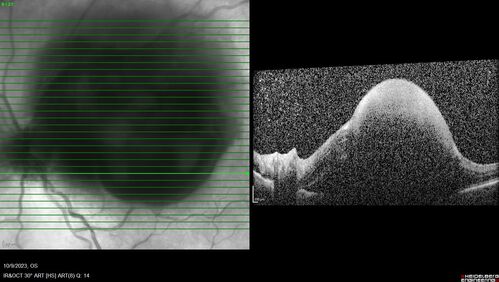

Ruptured Retinal Arterial Macroaneurysm - Submacular hemorrhage and BRAO

81 year old female with vision loss for a few days. Coumadin was high with INR at 3.1 VA 6/200